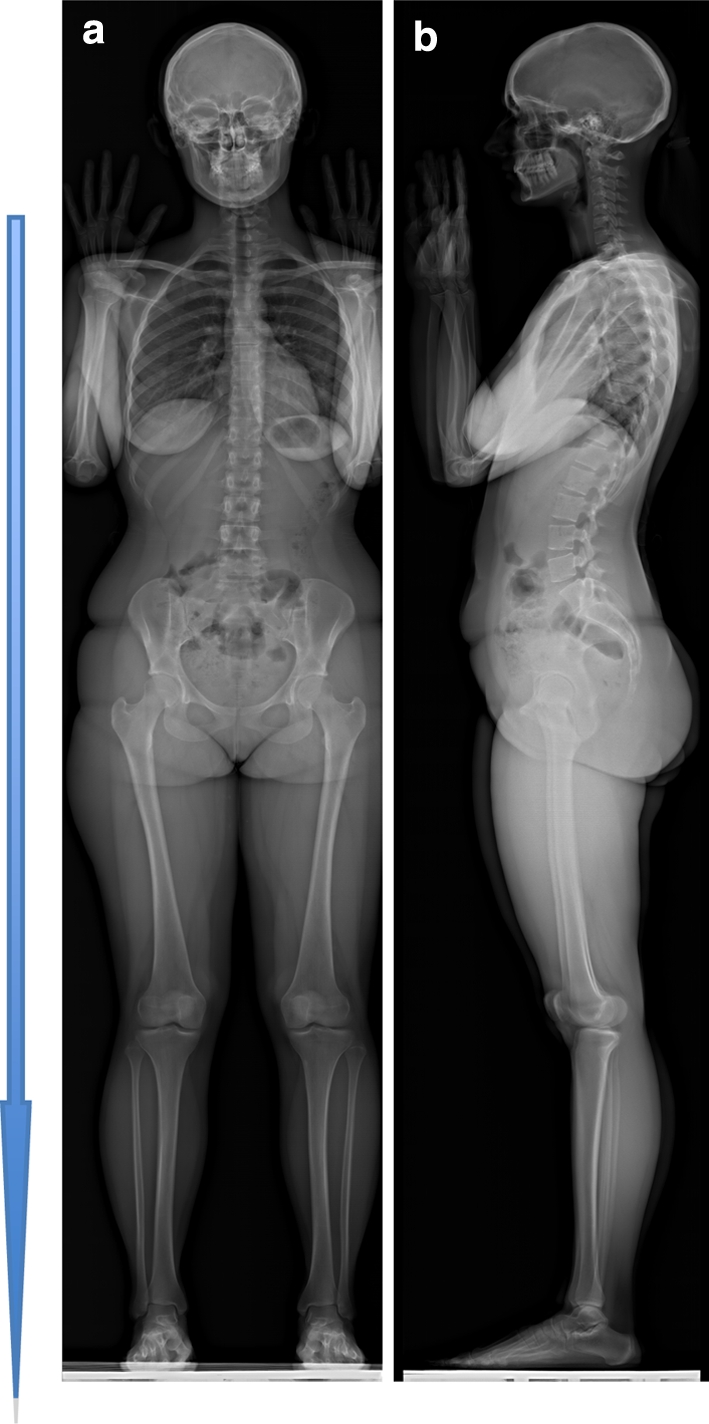

Fig. 1.

Simultaneous AP and lateral radiographic view of the full body in standing position with the low-dose EOS system (Biospace, Paris, France). a AP view and b lateral view of the spine and pelvis

Bipedalism offers a number of advantages, which we shall briefly discuss, but it entails a number of constraints that must be managed by the musculoskeletal system [1]. An upright posture results in complete liberty of the upper limbs, which are now free to perform tasks or carry things. The lower limbs become the sole point of contact with the ground. We have thus gone from a highly stable quadruped position to an eminently unstable biped position [3]. However, stability in the upright position is preserved despite a smaller base of support between the two feet. Nevertheless, although upright, humans can carry loads and are able to run. The upright position of humans also allows completely vertical position to be combined with a fixed unstable horizontal line of sight, in which it is essential for effective positioning of the semicircular canals and thus good balance [1]. Finally, human bipedalism is ergonomic [2]. In order to allow such an upright position to be assumed, the hips and knees form a straight line. The femoral bone is lengthy and vertical (Fig. 1), the femoral trochlea is hollow to ensure stabilisation of the patella during walking, and the proximal end of the tibia broadens at the plateau. The foot, which has lost its prehensile function, serves to propel the body [1]. The arch of the foot, which is clearly present, helps absorb shocks during walking and provides additional impetus while walking or running.